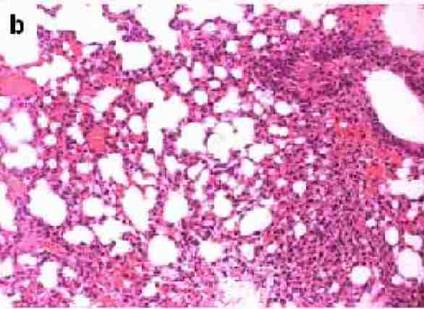

Postradiační změny v plicní tkáni

Postradiační změny v plicní tkáni.